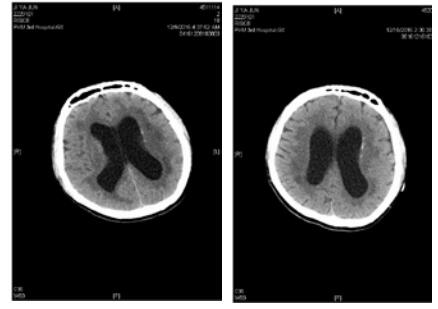

患者,男,31岁,既往体健。因“间断发热、咳嗽10 d,昏迷16 h”于2016年12月9日入院。患者2016-11-30无诱因出现咳嗽、发热,抗感染治疗3 d后,症状好转。2016-12-6患者再次出现上述症状,最高体温38℃,伴头痛。2016-12-8 19:31于本院就诊期间出现意识模糊,瞻妄,次日02:15患者深昏迷,呼之不应。查体:体温38.5℃,脉搏131次/min,呼吸29次/min,血压126/56 mmHg(1 mmHg=0.133 kPa), 心、肺、腹未见异常。专科情况:深昏迷,双侧瞳孔不等大,左侧d=5.5 mm, 右侧d=6.0 mm, 双侧对光反射消失,疼痛刺激无反应,角膜反射未引出,脑神经查体不合作,四肢肌力查体不合作,双上肢肌张力高,双下肢肌张力正常,双侧膝、跟腱反射亢进,踝阵挛,颈强直,克氏征阳性、布氏征阳性。颅脑CT示双侧侧脑室低密度影,颅内感染?双侧侧脑室扩张。血常规:白细胞15.43×109/L,中性粒细胞百分比4.62%;降钙素原3.74 ng/mL, 12月9日行腰椎穿刺抽出淡黄色微混脑脊液,压力>300 cmH2O(1cmHg=0.098kPa), 脑脊液常规:细胞总数864 ×106/L,白细胞818×106/L,多核细胞80%,单核细胞20%,生化:氯113.3 mmol/L,葡萄糖1.00 mmol/L,总蛋白258.0 g/L,革兰染色、墨汁染色、抗酸染色阴性,脑脊液培养结果阴性。血培养结果示:肺炎链球菌。诊断为化脓性脑膜炎,病原菌为肺炎链球菌。给予降颅压,抗感染治疗后,症状好转,2016-12-12患者疼痛刺激有反应。2016-12-20神志转清,可按指令发出动作,但遗留有双侧动眼神经损伤,表现为双侧瞳孔散大,双侧对光反射消失,双侧眼睑下垂,左侧明显,双侧瞳孔各方位(除外展位外)运动不良;此外,合并双侧视神经、左侧面神经损伤,表现为无光感,左侧额纹消失,左侧鼻唇沟略浅。2016-12-26患者恢复部分光感,但视野缺损,无法分辨颜色。双侧动眼神经损伤及左侧面神经损伤未见明显改善,查体脑膜刺激征仍阳性。2016-12-15复查颅脑CT较前无明显变化。2016-12-27颅脑磁共振示脑积水,颅底感染,考虑患者动眼神经及其余脑神经损伤与高颅压压迫脑神经及颅底感染侵及脑神经有关,建议患者外院行脑室穿刺引流术进一步治疗。

| 图 1 左侧为2016年12月8日我院颅脑CT,右侧为2016年12月15日我院复查颅脑CT,两次颅脑CT均提示双侧侧脑室扩张,无明显变化 |